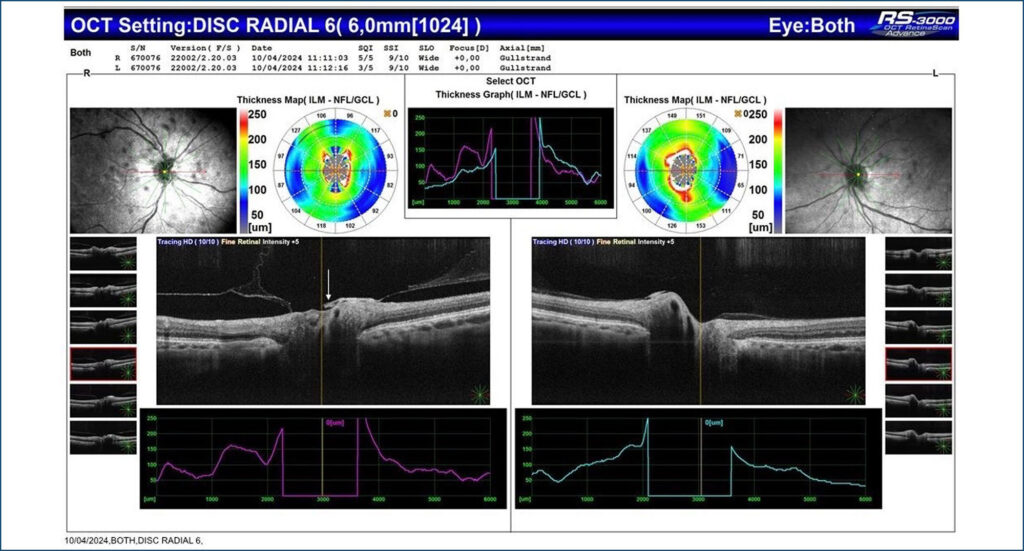

O objetivo deste manuscrito é documentar um caso de papila de Bergmeister que foi um achado incidental e teve seu diagnóstico conclusivo feito pela tomografia de coerência óptica de nervo óptico e retinografia. Relatamos o caso de uma paciente do sexo feminino que veio ao nosso serviço para consulta de rotina alegando dificuldade visual para longe em ambos os olhos. Após a consulta e a solicitação dos exames diagnósticos, encontrou-se, no olho direito, a papila de Bergmeister, condição clínica geralmente congênita e assintomática, cuja conduta é seguimento anual com exames para acompanhamento.